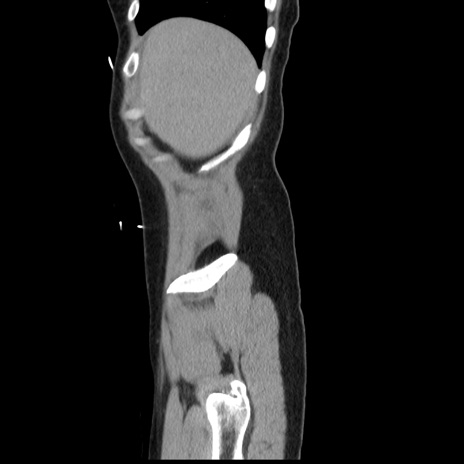

冠状断像

【症例】 50歳代女性

【主訴】 腹痛

【現病歴】前日生レバーを食べた。今朝に排便あり。 昼前に突然発症の腹痛を生じ、当院救急外来を受診した。

【既往歴】 子宮筋腫にてで子宮全摘後

【身体所見】 意識清明、腹部:平坦、軟、下腹部やや左を中心に圧痛・反跳痛あり、筋性防御あり

【データ】WBC 7800、CRP 0.07